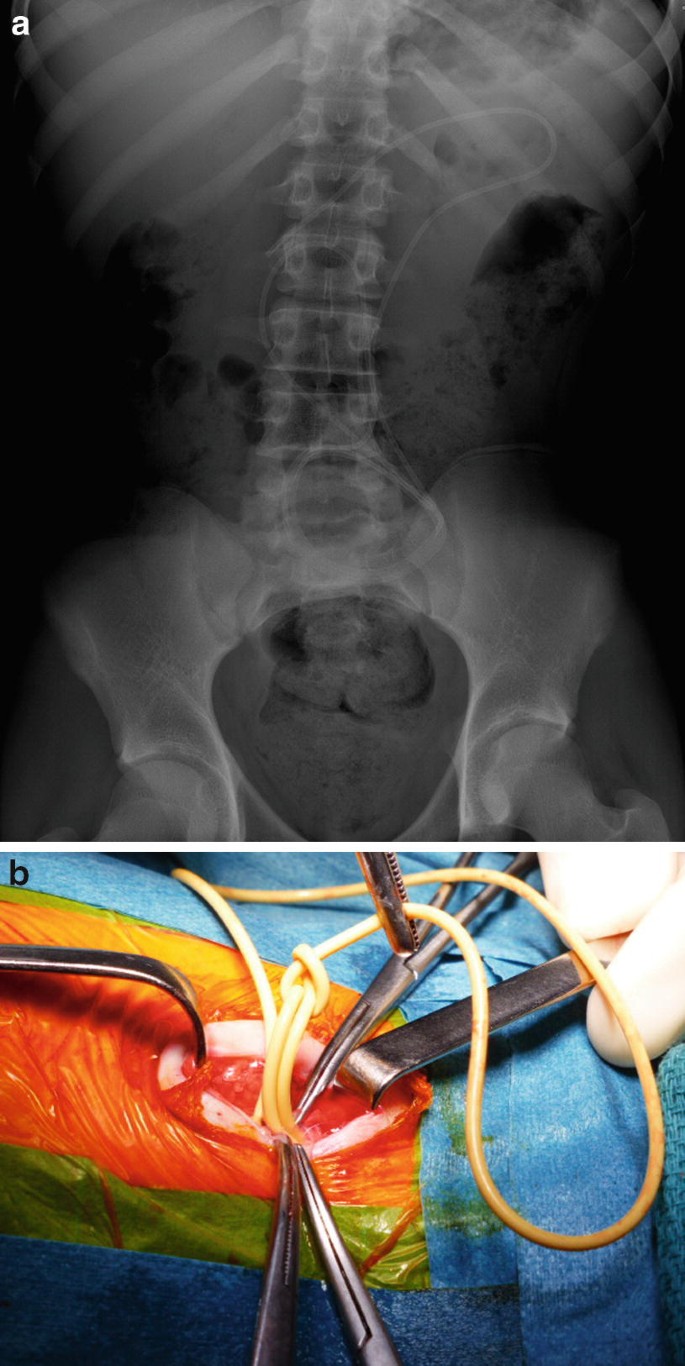

Complications Related to the Treatment of Hydrocephalus with Extrathecal Cerebral Spinal Fluid Shunts | Springer Nature Link (formerly SpringerLink)